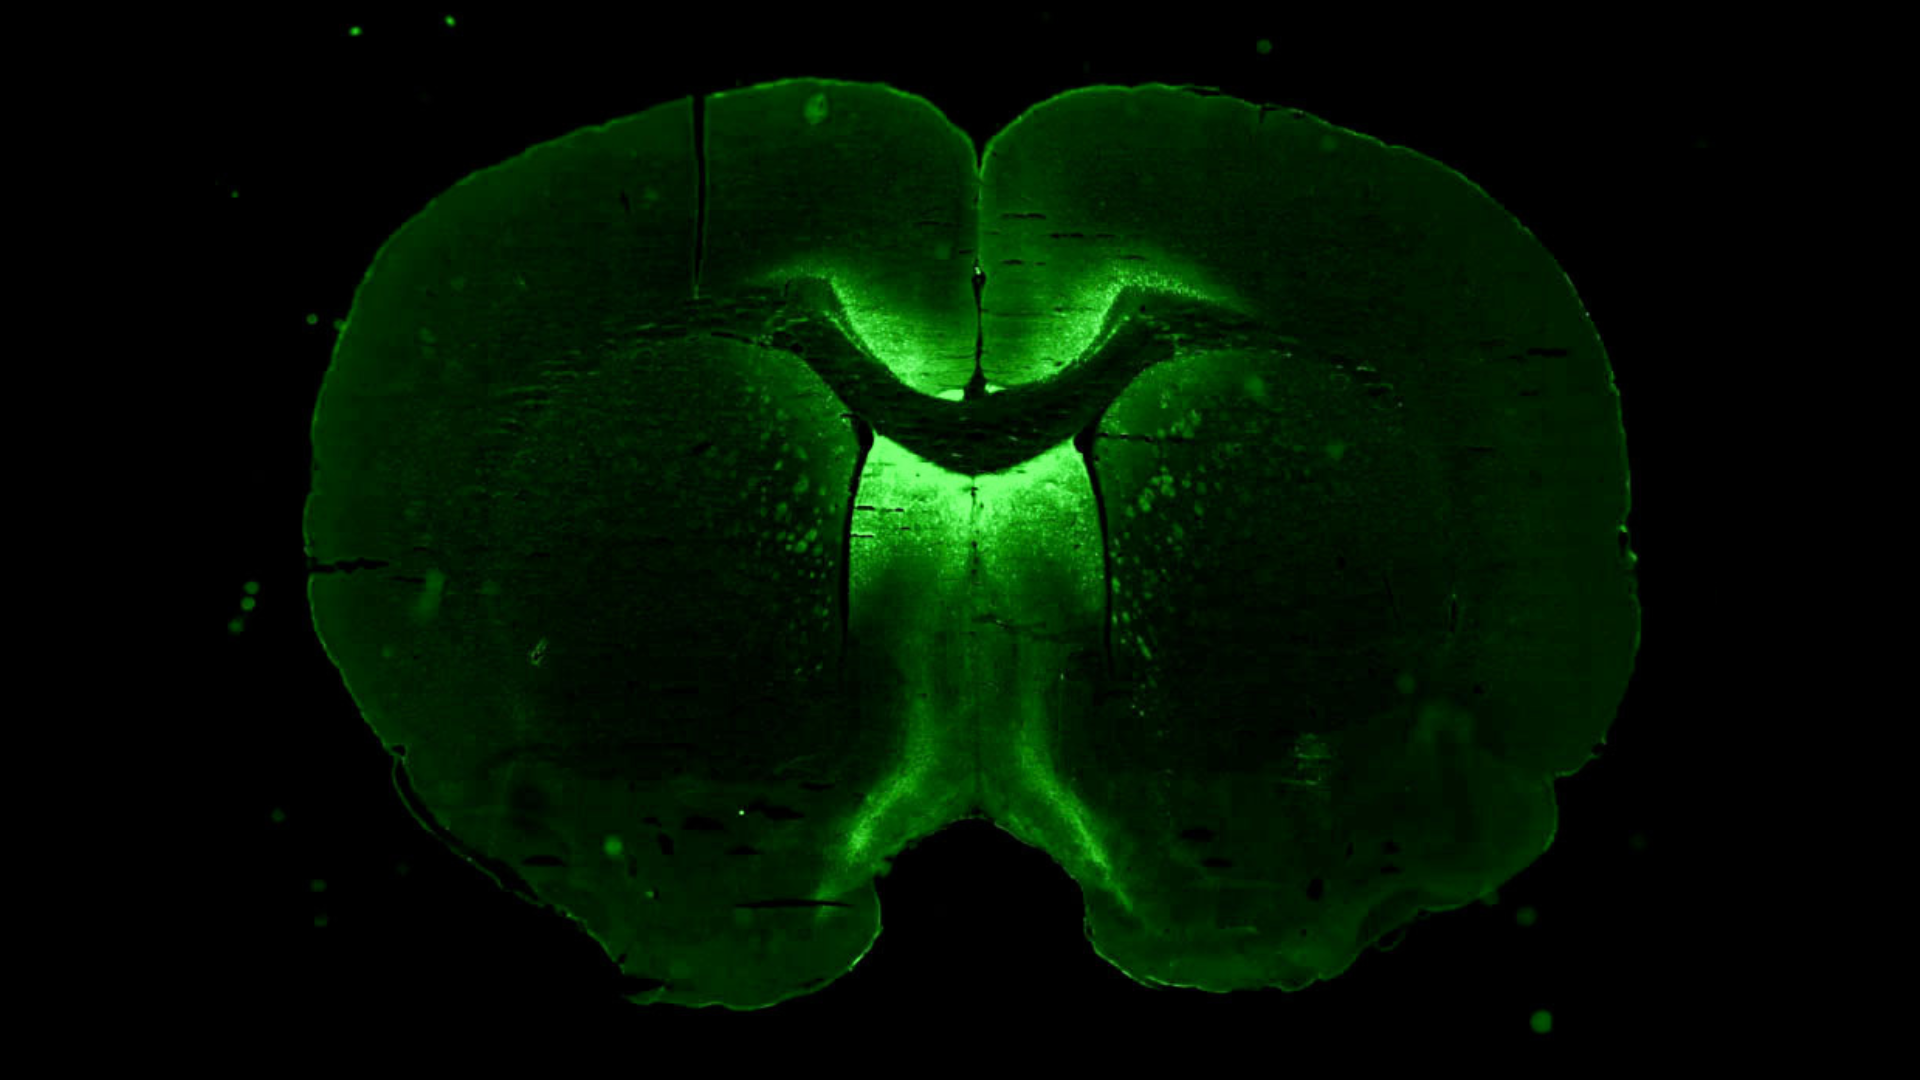

Co-principal investigator for a neuroscience experiment launching to the space station soon walks us through the goals of the experiment and how it might benefit patients back on Earth. HWHAP Episode 291.